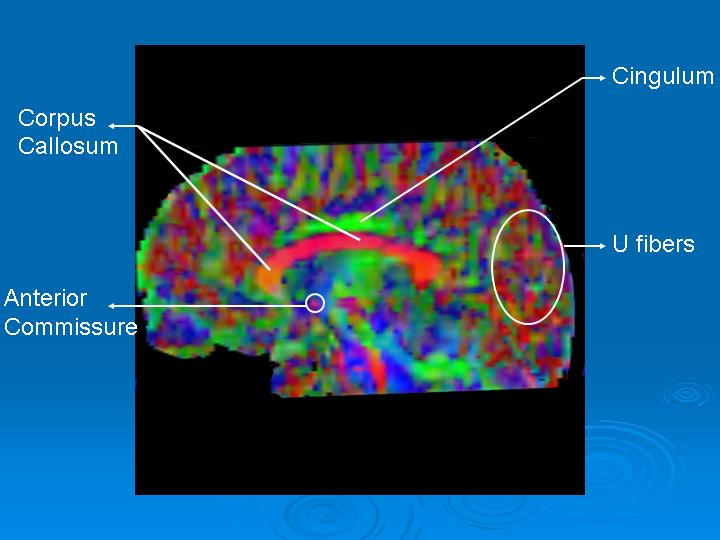

The sagittal plane (figure 3) best provides information on interhemispherical fibers going right to left or viceversa (red) or anterior-posterior (green). These are the corpus callosum and the anterior commissure.

Figure 3. Saggital FA Map. Interhemispheric fibers are red in the midsagittal cut. Horizontal portion of the cingulum above the corpus callosum appears green. The green bundle in the inferior left corresponds to the medial part of the superior cerebellar peduncle.

Subcortical U fibers appear various colors due to multiple intersecting planes.